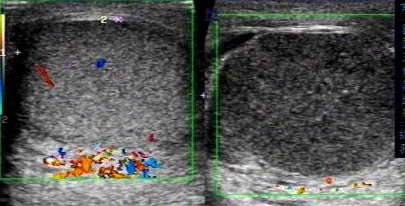

(左側(cè)為正常睪丸,右側(cè)為扭轉(zhuǎn)睪丸)

彩色多普勒超聲血流圖是最具有診斷價(jià)值的影像學(xué)檢查,可以詳細(xì)、實(shí)時(shí)地觀察睪丸內(nèi)的血流情況及其變化,目前被廣泛應(yīng)用于睪丸扭轉(zhuǎn)的診斷和鑒別診斷。睪丸內(nèi)動(dòng)脈血流信號(hào)明顯減少或消失是診斷本病的最可靠標(biāo)準(zhǔn)。